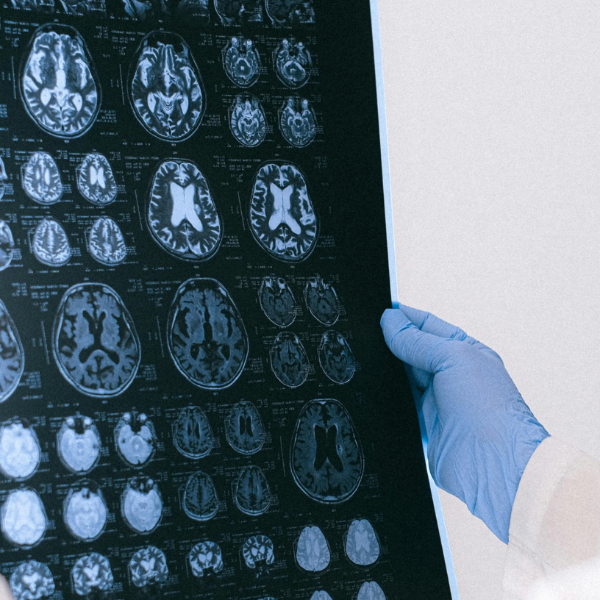

Una reciente investigación del Barcelonaβeta Brain Research Center (BBRC) ha encontrado que el sueño de mala calidad se asocia con cambios estructurales en regiones cerebrales vulnerables al alzhéimer, especialmente en mujeres. El estudio fue publicado en la revista científica Alzheimer’s & Dementia y aporta nuevas pruebas sobre el impacto del descanso nocturno en la salud cerebral, incluso en personas sin síntomas de deterioro cognitivo.

Los investigadores analizaron a 171 adultos cognitivamente sanos, la mayoría con alto riesgo de desarrollar alzhéimer, y evaluaron también la presencia de biomarcadores asociados a la enfermedad, como las proteínas amiloide y tau, a través de análisis de líquido cefalorraquídeo y resonancias magnéticas.

Los resultados revelaron que una menor eficiencia del sueño y mayor fragmentación se relacionan con un menor grosor cortical en el lóbulo temporal medial, una zona que suele verse afectada en etapas tempranas del alzhéimer.